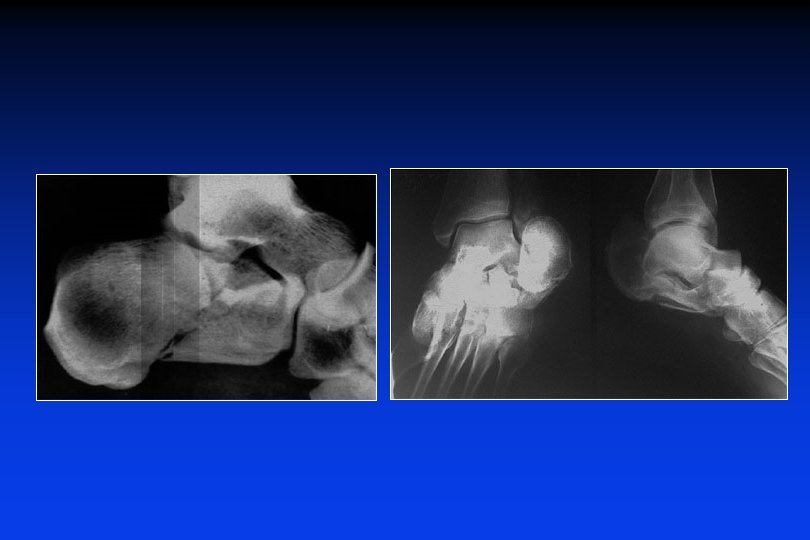

Sequele di fratture del Calcagno "Piede piatto valgo traumatico" - affossamento del tallone - allargamento del tallone